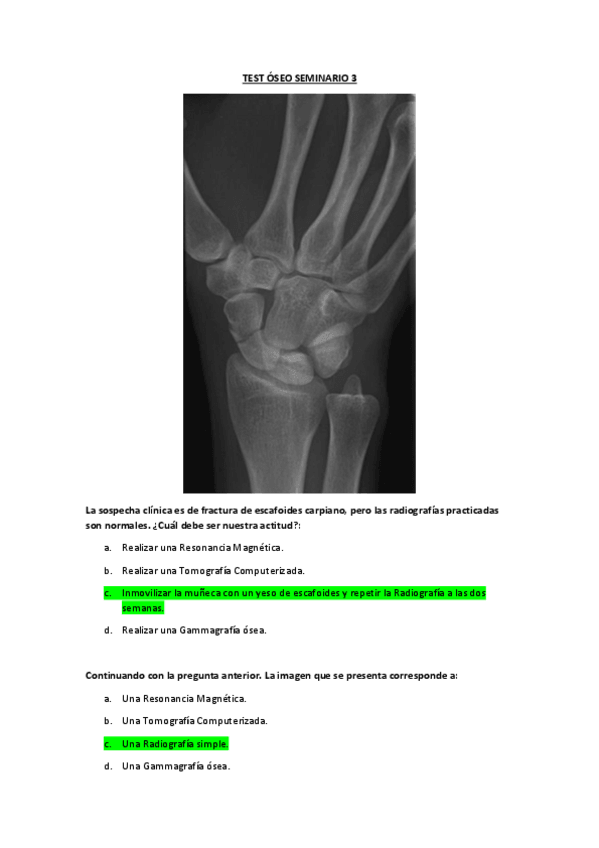

He publicado nuevos apuntes de 3º Radiología y Medicina Física. Protección Radiológica: SEMINARIO-3-RADIO- 2º cuatri.pdf